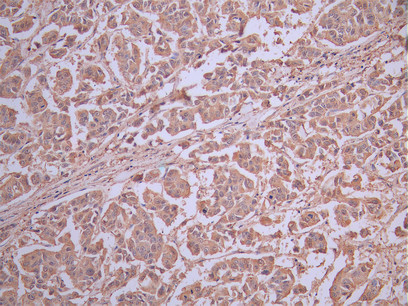

IHC image of CSB-RA011087MA2HU diluted at 1:50 and staining in paraffin-embedded human breast cancer performed on a Leica BondTM system. After dewaxing and hydration, antigen retrieval was mediated by high pressure in a citrate buffer (pH 6.0). Section was blocked with 10% normal goat serum 30min at RT. Then primary antibody (1% BSA) was incubated at 4°C overnight. The primary is detected by a Anti-Human lgG, Fcy Fragment Specific labeled by HRP and visualized using 0.05% DAB.

CSB-RA011087MA2HU

IHC image of CSB-RA011087MA2HU diluted at 1:50 and staining in paraffin-embedded human liver cancer performed on a Leica BondTM system. After dewaxing and hydration, antigen retrieval was mediated by high pressure in a citrate buffer (pH 6.0). Section was blocked with 10% normal goat serum 30min at RT. Then primary antibody (1% BSA) was incubated at 4°C overnight. The primary is detected by a Anti-Human lgG, Fcy Fragment Specific labeled by HRP and visualized using 0.05% DAB.